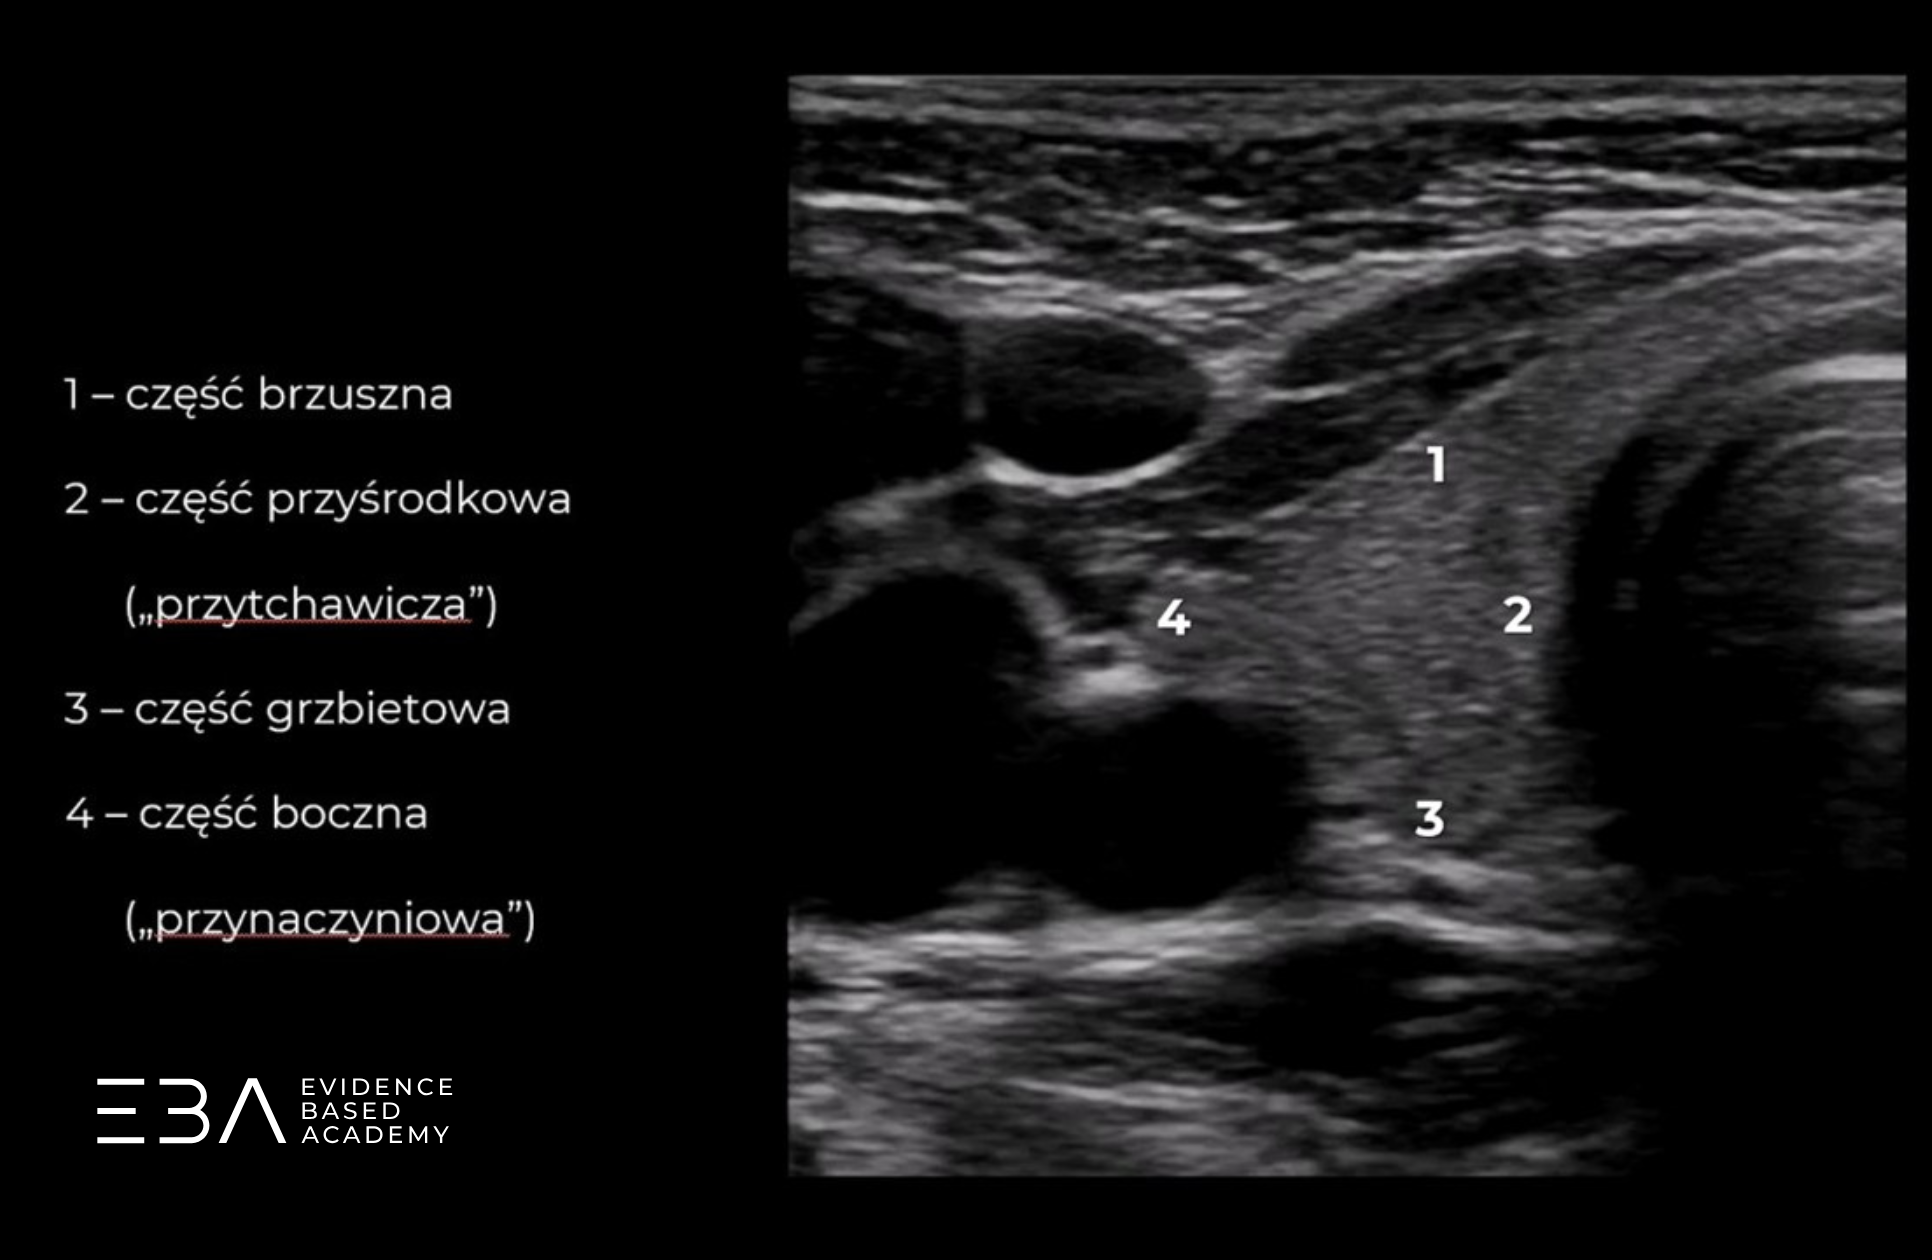

Skupiając się na jednym z płatów w przekroju poprzecznym, możemy podzielić go na części: brzuszną (przednią), grzbietową (tylną), boczną (przynaczyniową) oraz przyśrodkową (przytchawiczą).

Projekcja poprzeczna z podpisami omawianych struktur.